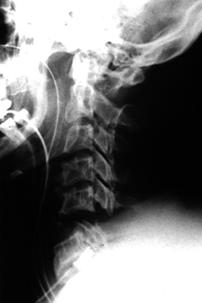

TRAUMA CERVICALA

Aspect normal Incidenta

oblica

Aspect normal

Incidenta oblica Incidenta laterala Incidenta antero-posterioara

Aspect normal Aspect normal Aspect normal